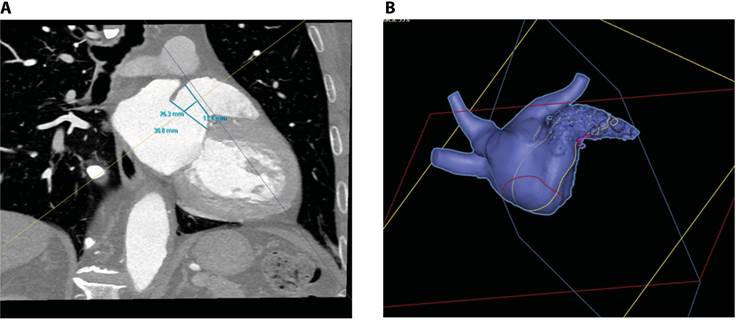

Dos pacientes, el primero, un masculino de 78 años con antecedente de FA permanente, hipertensión arterial (HTA) e insuficiencia cardiaca (IC) con fracción de eyección del ventrículo izquierdo (FEVI) reducida de 34%, cateterismo previo sin evidencia de lesiones coronarias obstructivas, con historia previa de sangrado digestivo (SD) posterior al inicio de medicación anticoagulante. El segundo, masculino de 62 años con antecedente de HTA, dislipidemia e IC con FEVI conservada de 60% y descompensación previa por FA permanente con alta respuesta ventricular, datos ecocardiográficos de insuficiencia mitral leve a moderada y crecimiento biauricular severo, por esto último considerado como no candidato para ablación con radiofrecuencia de las venas pulmonares, asimismo con diagnóstico de enfermedad inflamatoria intestinal e historia previa de SD que contraindicó inicio con anti- coagulantes, como se observa en la Figura 1 y 2, mediante la TAC se valora la anatomía de la orejuela, con el uso Heart Navigator, se observa morfología en ala de pollo, el ancho de la zona de apoyo, la longitud del lóbulo en milímetros, las venas pulmonares y la profundidad mínima de la orejuela.

Figura 1. A. imagen de la TAC realizada al paciente para valorar tipo de dispositivo y evaluar la efectividad del procedimiento. B. muestra el uso de la TAC 3D Heart Navigator a valorar la morfología de la orejuela izquierda y localización de las venas pulmonares.